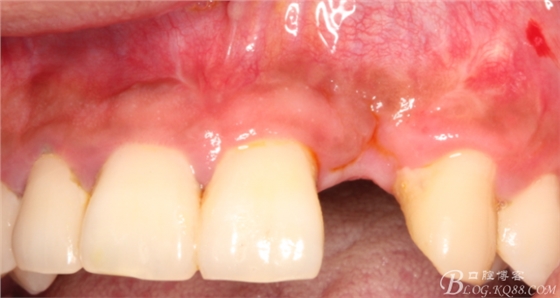

事實(shí)證明,我的做法沒有錯(cuò)誤,一個(gè)月后,軟組織健康愈合。鄰牙軟組織沒有退縮。

4個(gè)月后,唇側(cè)豐滿度尚可,與鄰牙之間齦乳頭完整。